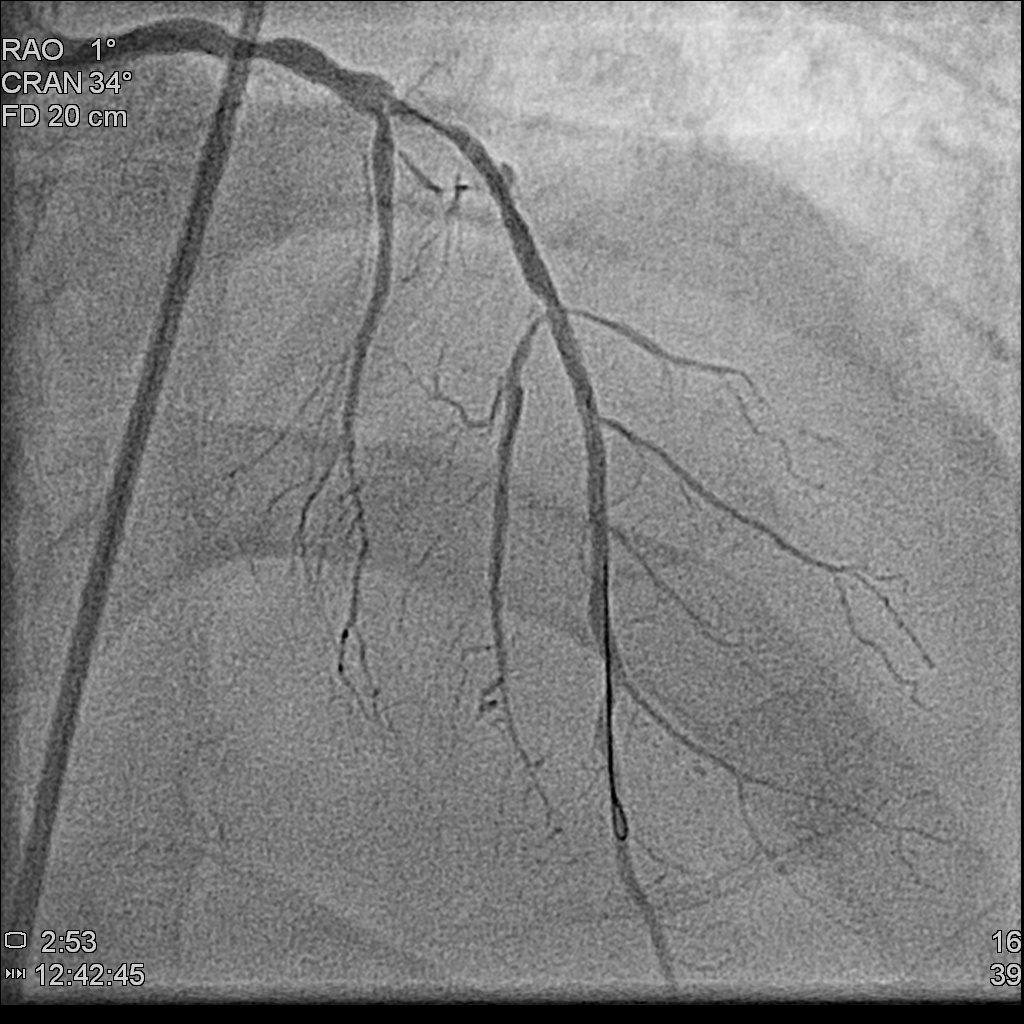

Left main: 50% stenosis at distal left main

Left anterior descending artery: diffuse atherosclerotic plaque,proximal to middle total occlusion, with a big septal branch sending collaterals to distal LAD and distal RCA

Left circumflex artery: absence of LCX from angiography

Left anterior descending artery: diffuse atherosclerotic plaque,proximal to middle total occlusion, with a big septal branch sending collaterals to distal LAD and distal RCA

Left circumflex artery: absence of LCX from angiography

Few months later, we saw the collateral vessels providing RCA previously were all disminished and the RCA flow was fine .We attempted his LM-LAD lesion with Miracle 6 and Gaia II guidewires.The microcatheter successfully entered the LAD stenotic segment. The Gaia II guidewire was negotiated through the point successfully. Dilatation was performed with 2.5x15mm,3.0x30mm Trek balloons sequentially. A Synergy 3.5x48mm DES was deployed from the middle left main (LM) to the middle LAD, followed by post-dilatation with 4.5x15mm NC Euphora balloon. The final result showed acceptable results

Few months later, we saw the collateral vessels providing RCA previously were all disminished and the RCA flow was fine .We attempted his LM-LAD lesion with Miracle 6 and Gaia II guidewires.The microcatheter successfully entered the LAD stenotic segment. The Gaia II guidewire was negotiated through the point successfully. Dilatation was performed with 2.5x15mm,3.0x30mm Trek balloons sequentially. A Synergy 3.5x48mm DES was deployed from the middle left main (LM) to the middle LAD, followed by post-dilatation with 4.5x15mm NC Euphora balloon. The final result showed acceptable results